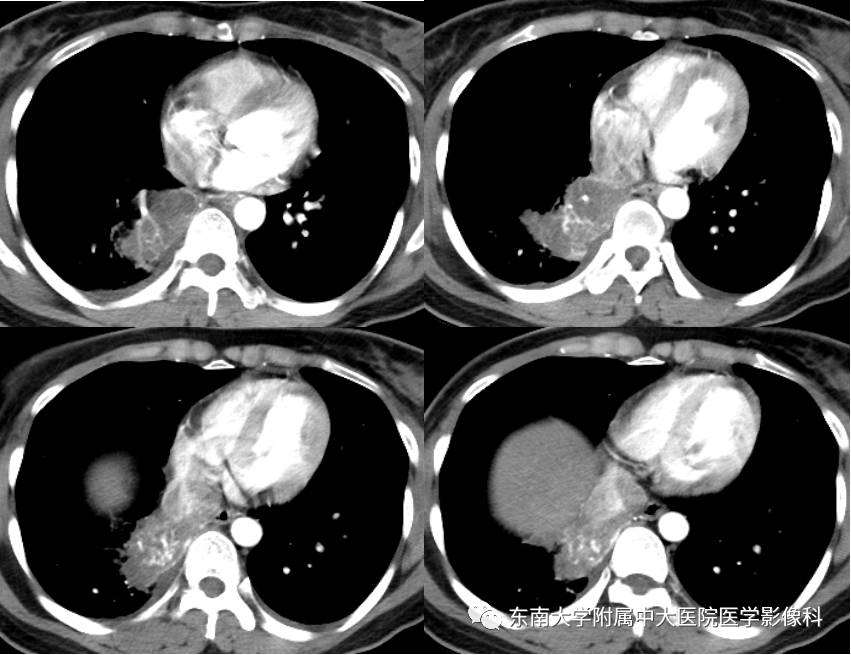

CT增强

【病例】肺隔离症1例CT影像表现

女,38岁,因“间断咯血2月余”入院。